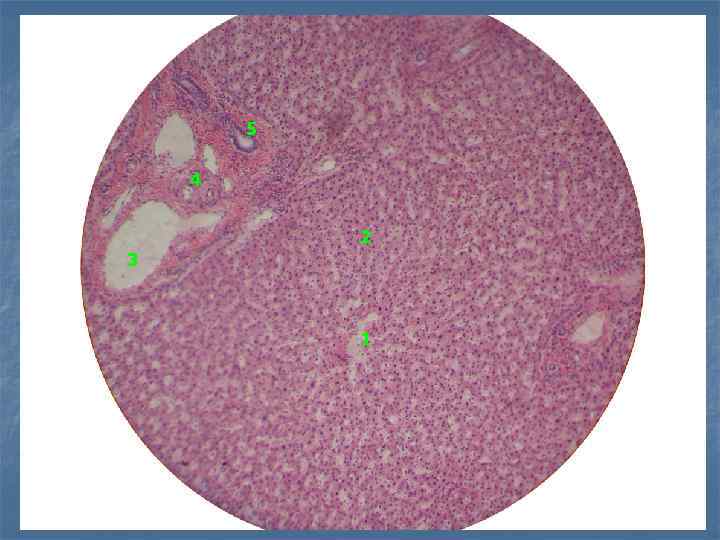

5 4 2 3 1